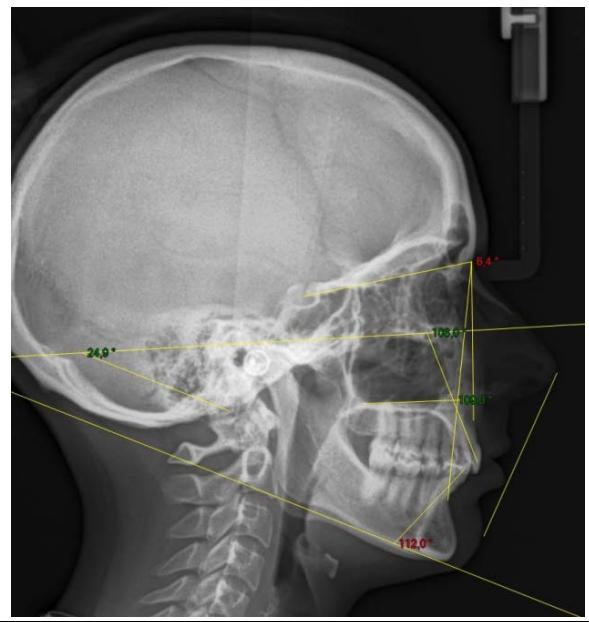

L'examen cephalométrique confirme le diagnostic de classe II squelettique par rétromandibulie et la forte vestibulo-version des incisives mandibulaires $(112^{\circ})$.

Examen cephalométrique de début de traitement.

La comparaison des télé radiographies permet d'objectiver le redressement incisif mandibulaire et la distalisation molaire mandibulaire obtenue. Nous observons également le maintain des axes incisifs au niveau de l'arcade maxillaire.

On note un redressement incisif très important. En effet, l'axe incisif mandibulaire est passé de $112^{\circ}$ à $90.3^{\circ}$ en 6 mois. Une distalisation molaire de 3 MMA également été obtenu. Les axes incisifs maxillaires ont été maintainus, ce qui correspond parfaitement à notre objectif de départ.

Télé radiographies de profil: comparaison entre l'image de début de traitement et l'image de contrôle après 6 mois de traction sur l'ancrage par fil dans la branche montante mandibulaire. L'angle incisif est passé de 112 à $90,3^{\circ}$.